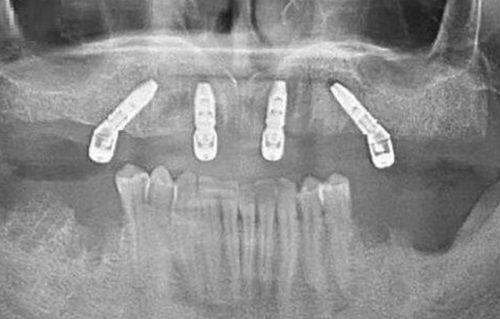

康斯坦丁医生深耕口腔种植及修复领域多年,技术扎实全面,拥有深厚的德国口腔诊疗技术背景,不仅是德国Ankylos种植系统培训师、德国SDS种植体研发医生团成员,还参与德国FORESTADENT非凡正畸专项技术研发。他耐心细致,擅长和患者沟通,能根据患者口腔情况制定个性化诊疗方案,具备处理各类复杂口腔种植病例的能力,还能将国际先进的种植技术与国内患者口腔实际情况相结合,优化诊疗方案,提升治疗效果与患者体验,多年来深受患者喜爱,行业认可度颇高。